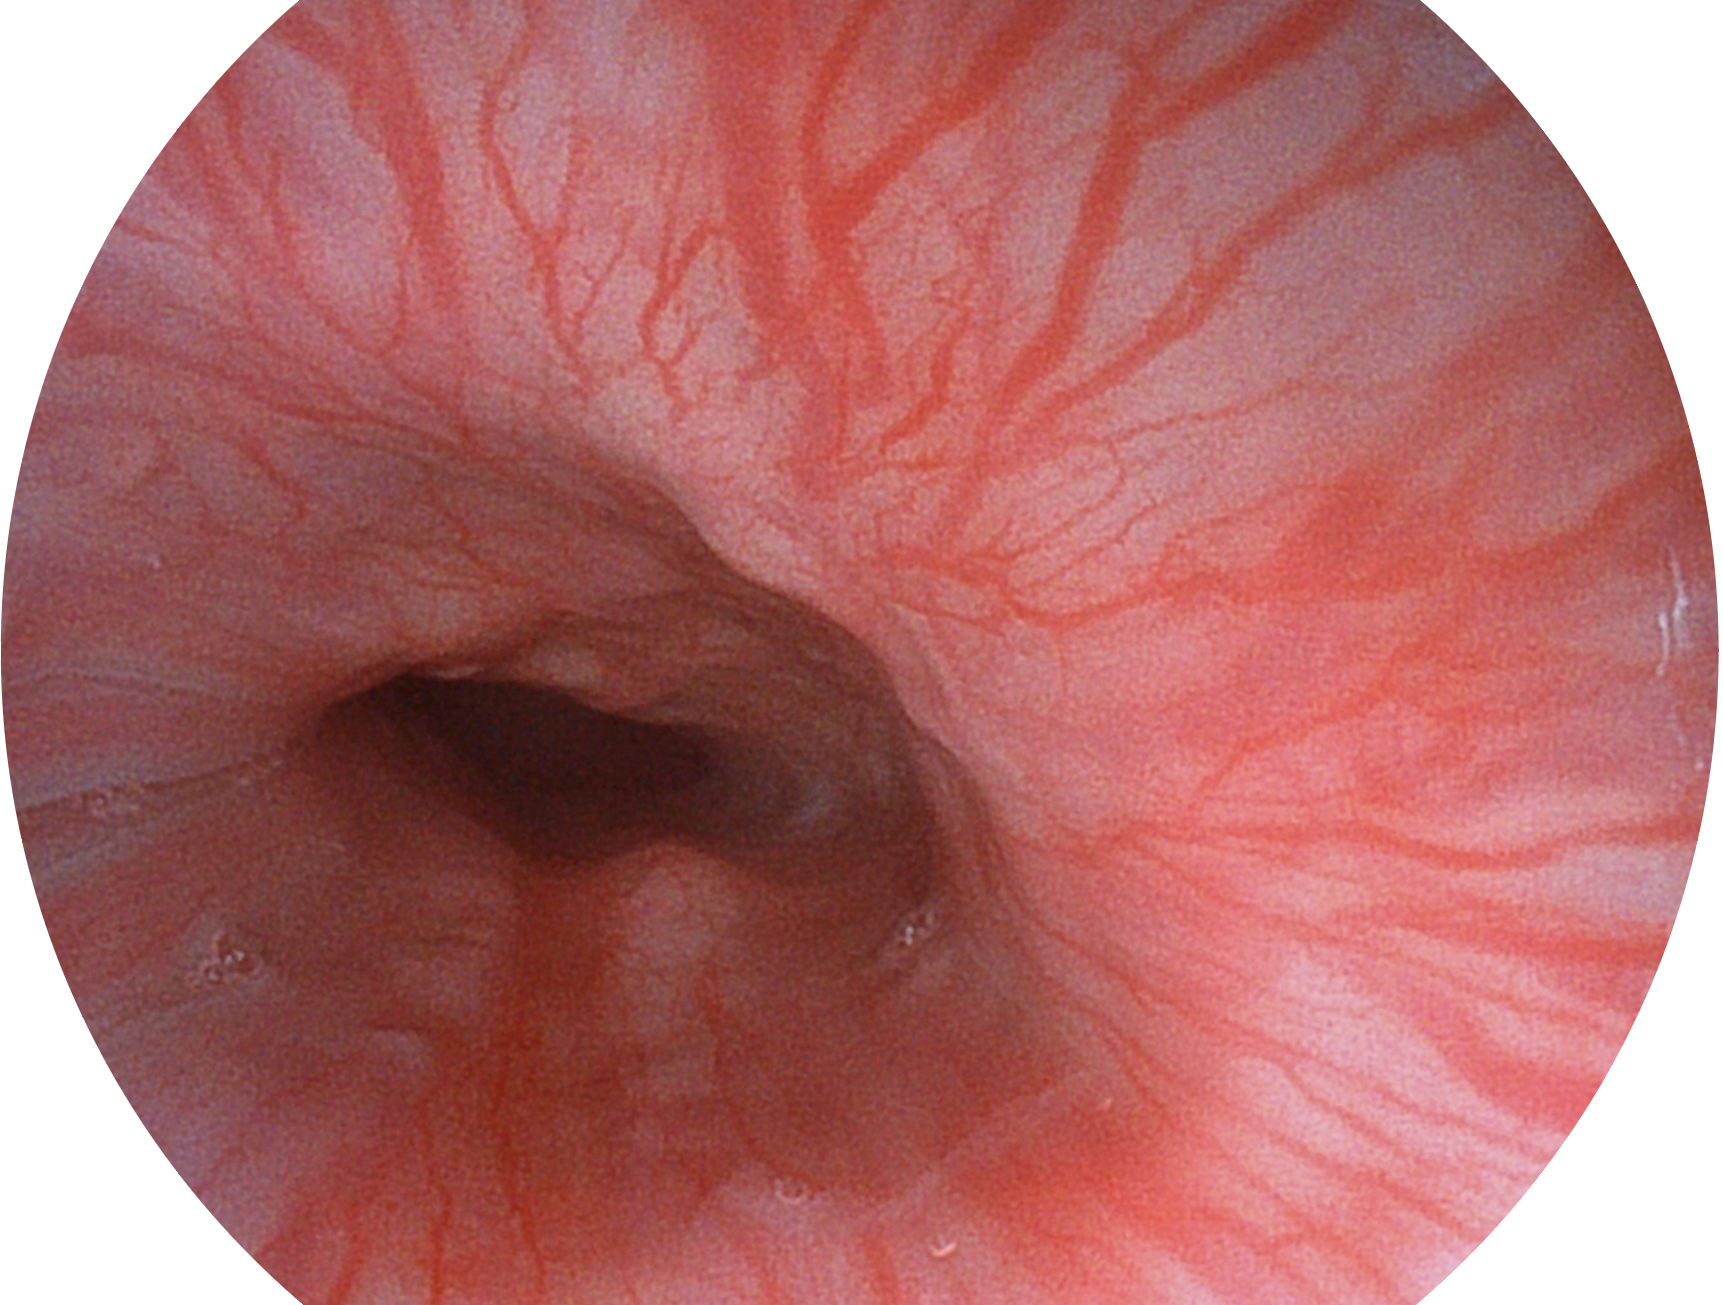

開立新開發(fā)的內(nèi)鏡染色技術(shù),主要是基于多波長LED 光源的開發(fā),VLS-55Q 四波長LED 光源是由四個不同顏色的LED光按照相應(yīng)照明模式所規(guī)定的特定發(fā)光比例進(jìn)行合束后形成,合束后形成的照明光的光譜由紅光、綠光、藍(lán)光及藍(lán)紫光這四個不同的波段范圍構(gòu)成。具有更高光譜自由度,通過光譜比例的控制,實現(xiàn)了聚譜成像技術(shù),英文全稱為“Spectral Focused Imaging, SFI”,縮寫為“SFI”和光電復(fù)合染色成像技術(shù),英文全稱為“Versatile Intelligent Staining Technology, VIST”,縮寫為“VIST”。